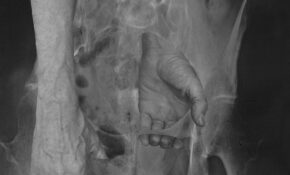

01 Studio Session 094

Birthe Piontek

On teaching staged photography